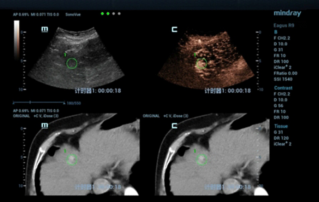

W przypadku ogniskowych zmian w w?trobie, takich jak naczyniaki czy nowotw├│r w?troby, obrazowanie USG z kontrastem odgrywa wa?n? rol?. Technologia obrazowania USG z kontrastem UWN+ mo?e pom├│c uzyska? lepsz? penetracj?, lepsz? jako?? obrazu z ni?szym indeksem mechanicznym MI oraz d?u?szy obserwowany czas perfuzji.